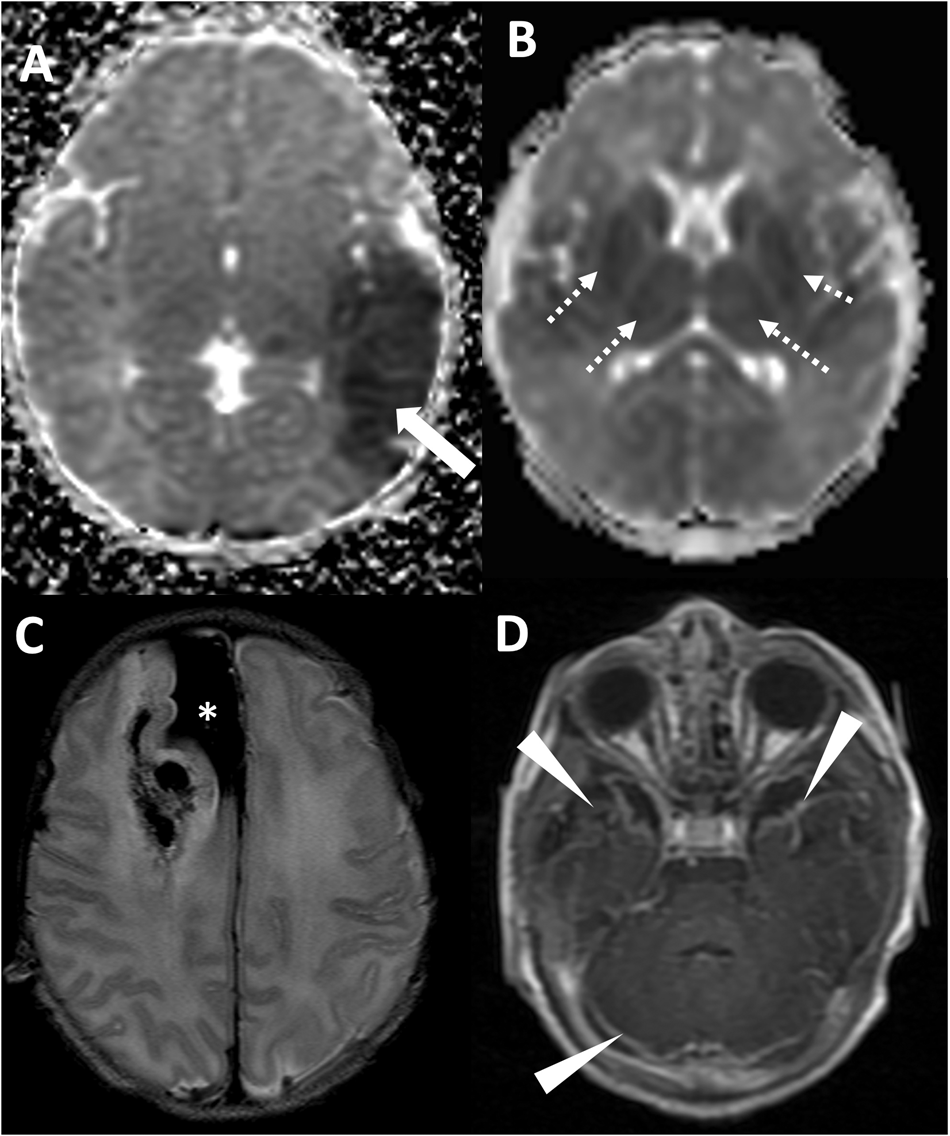

Fig. 3: Radiologic diagnoses in the cohort of patients with acute symptomatic seizures.

From: Neonatal brain MRI and short-term outcomes after acute provoked seizures

A Axial ADC map demonstrating arterial ischemic stroke in the left middle cerebral artery territory (white arrow). B Axial ADC map demonstrating reduced diffusion in the deep gray nuclei and subcortical white matter, compatible with hypoxic ischemic injury. C Axial T2 weighted imaging demonstrating large subpial hemorrhage in the medial right frontal lobe (asterisk) with associated hemorrhagic injury of the right frontal lobe. D Axial T1-weighted post-contrast imaging demonstrating leptomeningeal enhancement (arrowheads) in the setting of neonatal meningitis/intracranial infection.